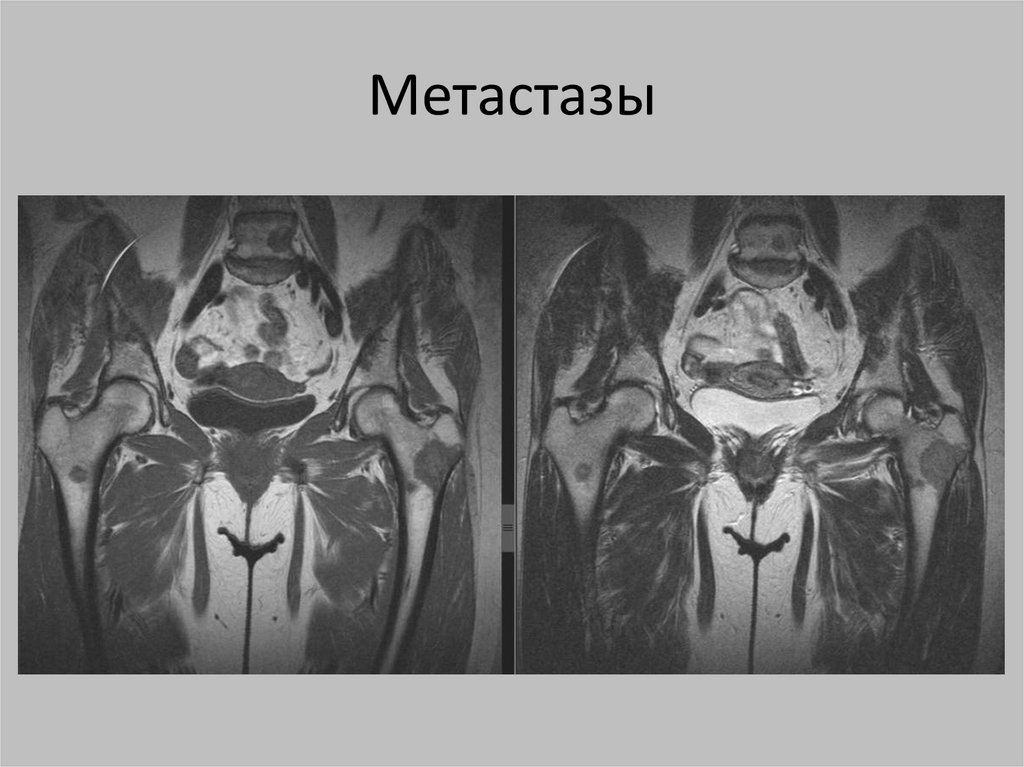

Метастазы

109.